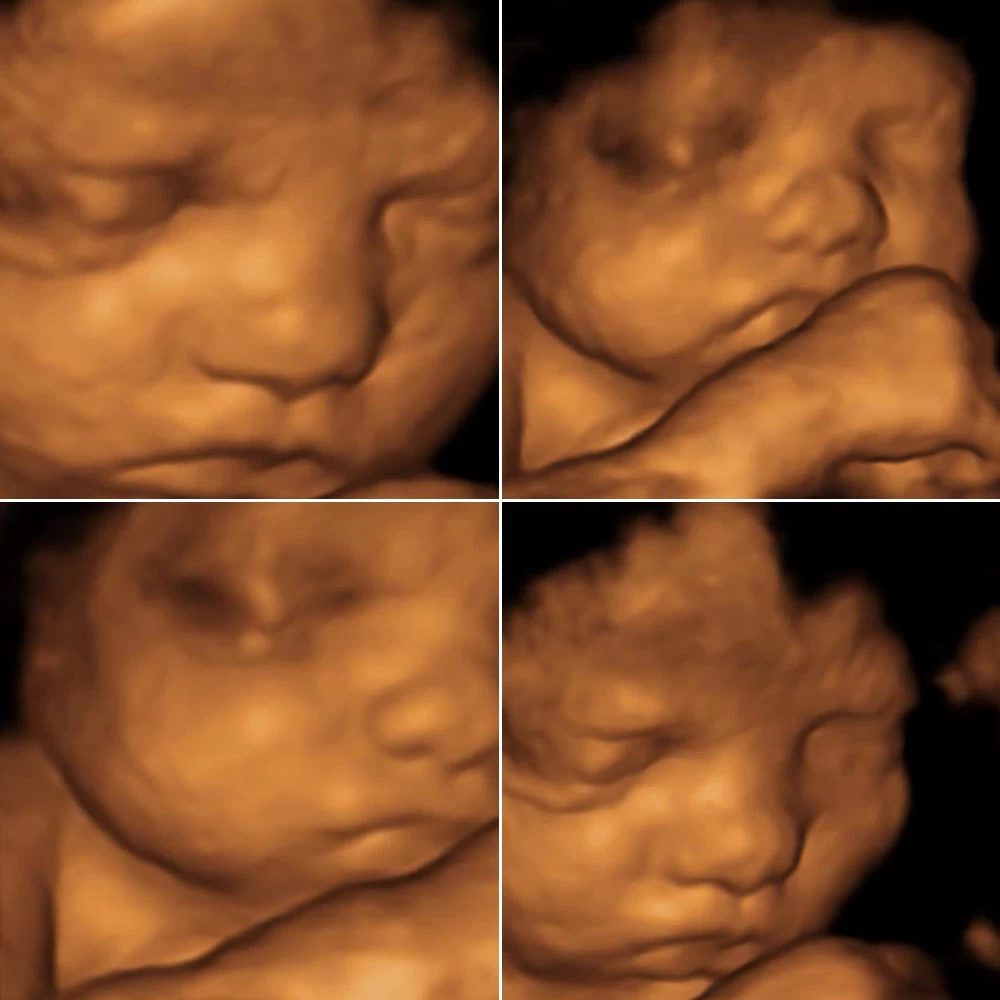

Копчиково-теменной размер к концу недели составляет 70-75 мм Начинают появляться зародыши молочных зубов под верхней и нижней челюстями. Лицо полностью сформировано, нос и глаза (полностью сомкнуты веками).

Неделя № 14

Копчиково-теменной размер к концу четырнадцатой недели увеличивается до 8-9 см. На лице хорошо очерчены лоб, нос, появляются щеки и подбородок. На голове появляются первые волосы (очень тонкие и бесцветные). Поверхность тела покрывается пушковыми волосками, которые удерживают смазку кожи и тем самым выполняют защитные функции.